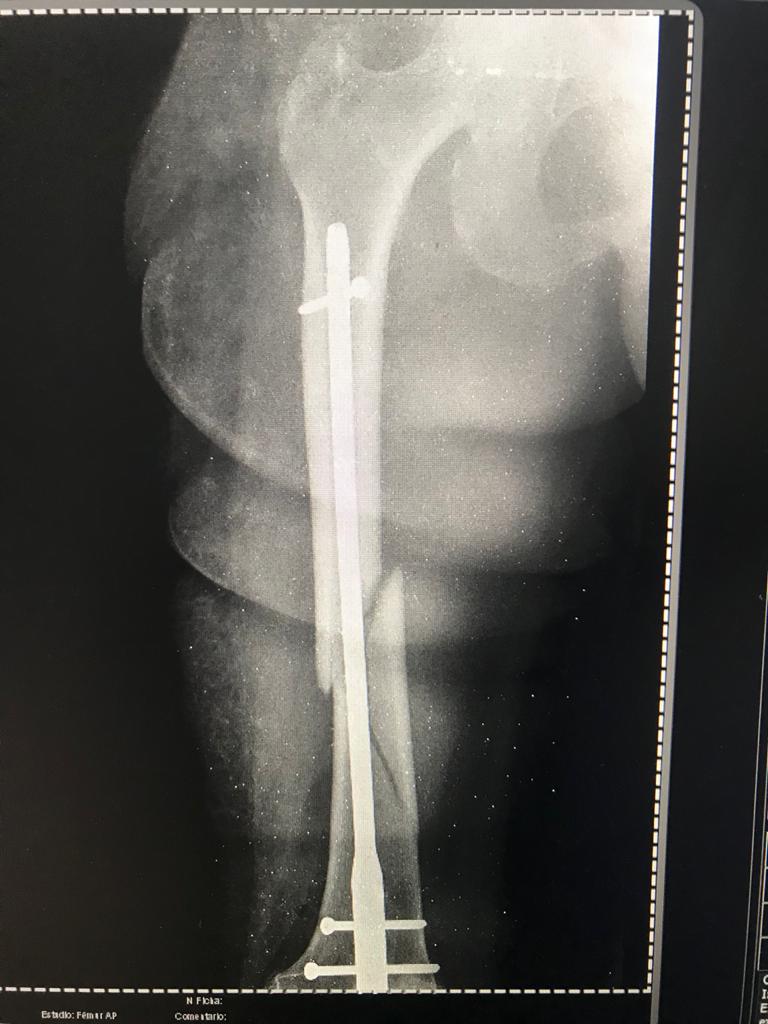

Una mujer de 76 años de edad se convirtió en la primera paciente de Misiones en ser intervenida con el Arco Quirúrgico en C, un equipo de rayos X de alta gama, proveído recientemente por el Gobierno Nacional, con inversión de la Entidad Binacional Yacyretá (EBY).

La cirugía fue realizada en el Hospital Regional de Misiones, con asiento en el distrito de San Juan Bautista, dependiente del Ministerio de Salud Pública y Bienestar Social (MSP Y BS). Este es el primer hospital de este departamento que cuenta con el equipo para procedimientos quirúrgicos traumatológicos percutáneos, sin necesidad de cortes importantes en la piel.